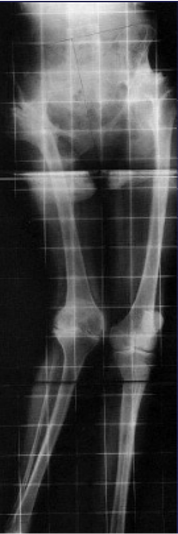

女性患者,48岁,右髋疼痛25年,加重1年

腰骶椎关节退变:

膝关节外翻畸形:

确定正常侧髋关节的旋转中心镜像至患侧: